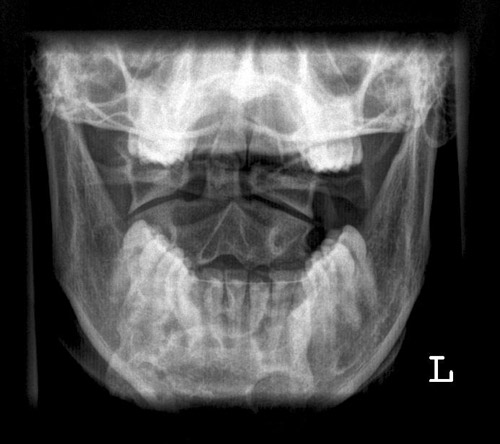

Dens a.p.

Fehler

Ungleicher Abstand der beiden aufsteigenden Unterkieferäste vom Dens.

Abhilfe

Der Kopf muss absolut symmetrisch zur Körperlängsachse gehalten werden.